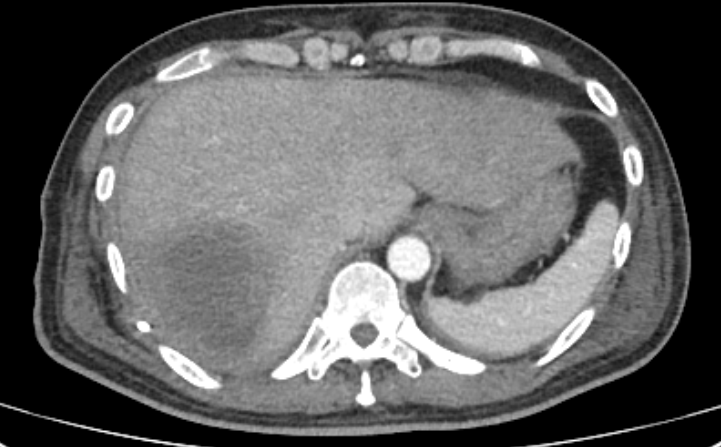

Liver Dynamin MDCT(E)

1.Incorrect position of Rt. PCD tube

2.About 7.5cm soap-bubble appearanced pyogenic hepatic abscess, Rt.lobe, S7

--small perihepatic complicated fluid collection

--large amount of Rt. pleural effusion with atelectasis, subcutaneous edema.

--rec)PCD change

3.Small ascites in the pelvis, significant amount of both hydrocele.

4.Reactive GB wall edema.

5.Lt. inguinal fat hernia.